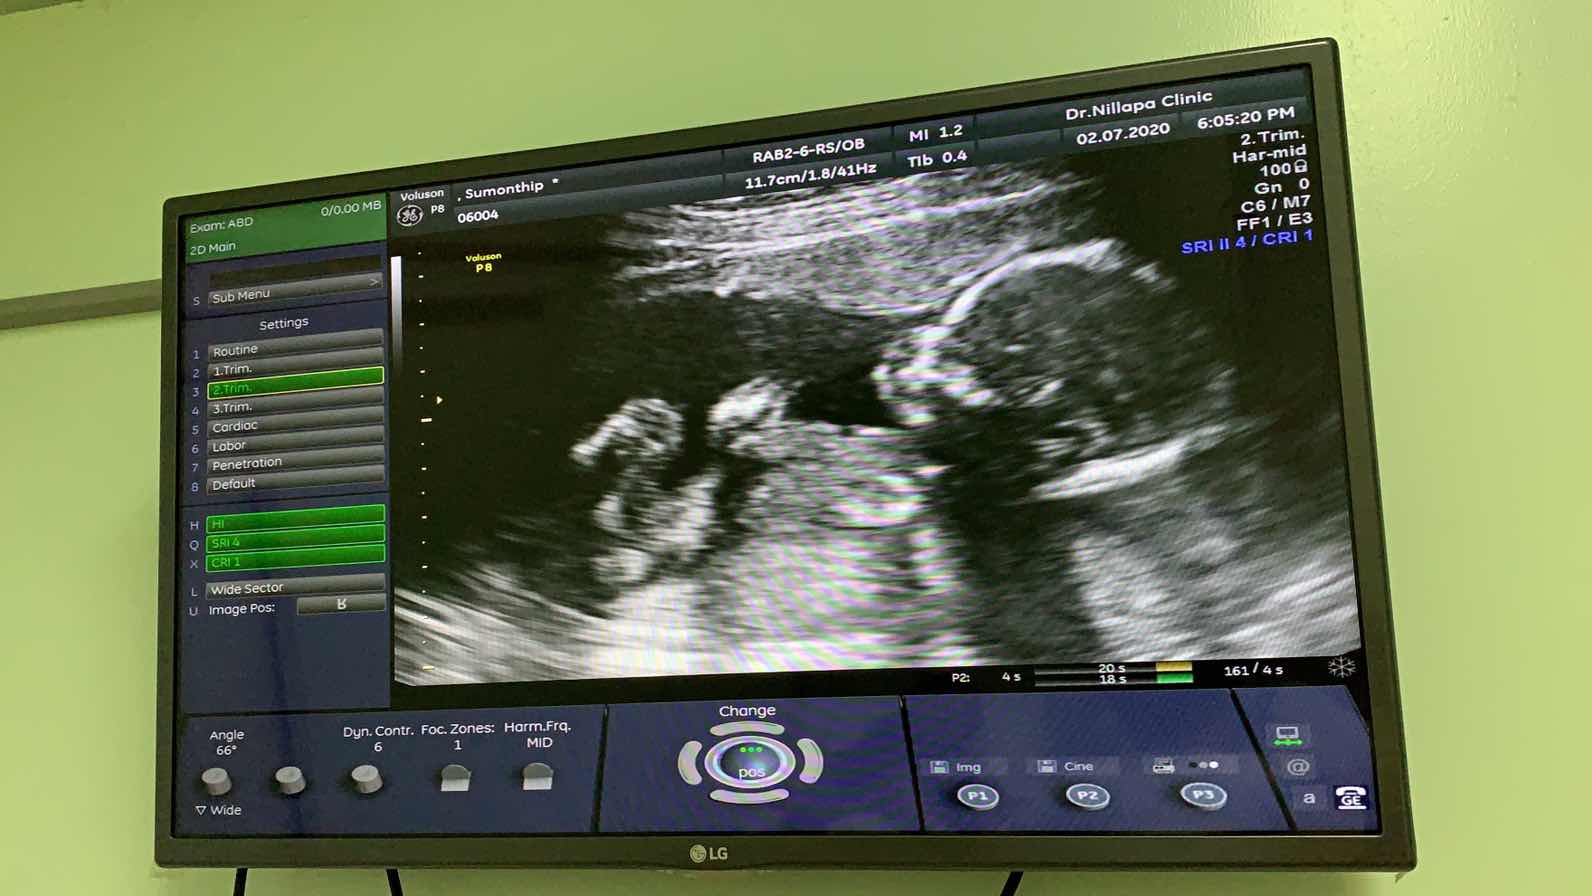

มาแชร์ภาพอัลตราซาวด์

มาแชร์ภาพอัลตราซาวด์ ทีมธันวาคา อยากทราบว่าแม่ๆ กำหนดคลอดวันไหน และตั้งครรภ์ได้กี่สัปดาห์กันแล้วคะ 🥰🥰🥰